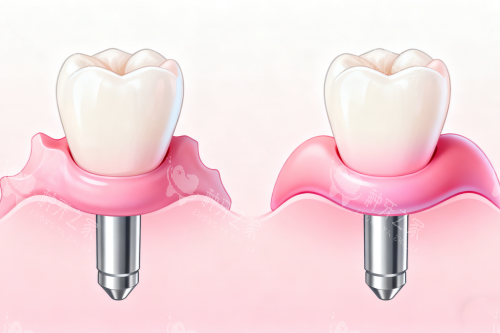

种植牙,作为当下修复牙齿缺失的理想方式,是将人工牙根(种植体)比较准植入牙槽骨内,再安装牙冠,以此替代缺失的牙齿。它宛如 “再生牙齿”,具有诸多优势。与传统假牙相比,种植牙无须磨除相邻的天然牙,对健康邻牙毫无损伤;固位结果较好,人工牙根与骨组织形成紧密的骨结合,稳固性强;能比较大限度地改善牙齿的咬合功能,几乎接近天然牙;异物感极小,舒适感仿若天然牙;美观度高,不会造成发音和咀嚼障碍;还可对牙槽骨产生功能性刺激,有效防止牙槽骨失用性吸收,维持牙龈健康。若维护得当,种植牙的使用寿命甚至可伴随一生。

之后是安装基台,好比搭建房屋主体结构。骨结合完成后,医生会切开牙龈暴露种植体,安装愈合基台,1 - 2 周后牙龈形态改善自然,为牙冠提供理想 “底座”。

然后是佩戴牙冠,如同房屋的精装修。医生会通过智能化扫描或传统取模,制作个性化牙冠,材质可选全瓷或烤瓷。全瓷冠通透逼真,适合前牙;烤瓷冠耐磨经济,适合后牙。安装牙冠时,医生会调整咬合高度、邻接关系,确保患者咀嚼舒适。